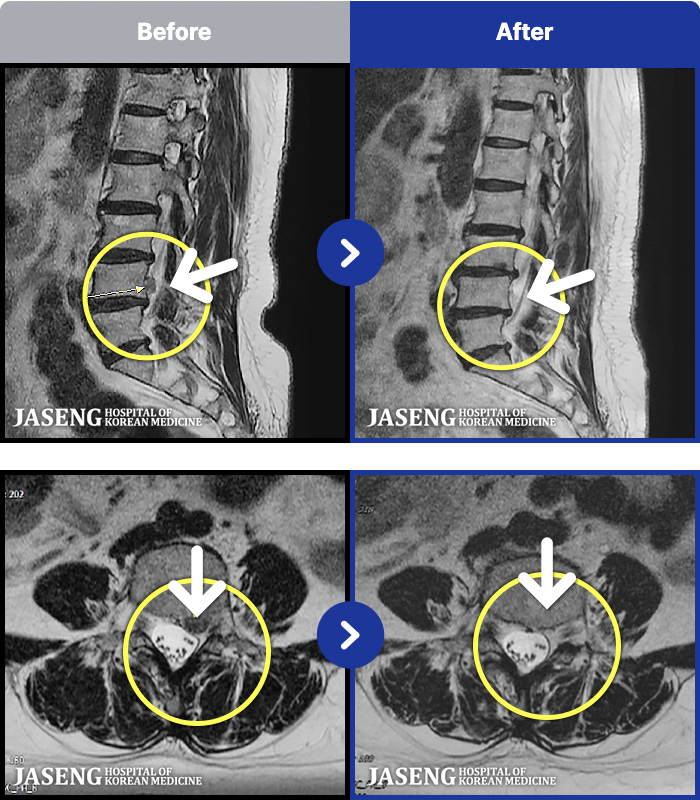

MRI ġ

56 MRI ũ ʸ Ȯϼ.